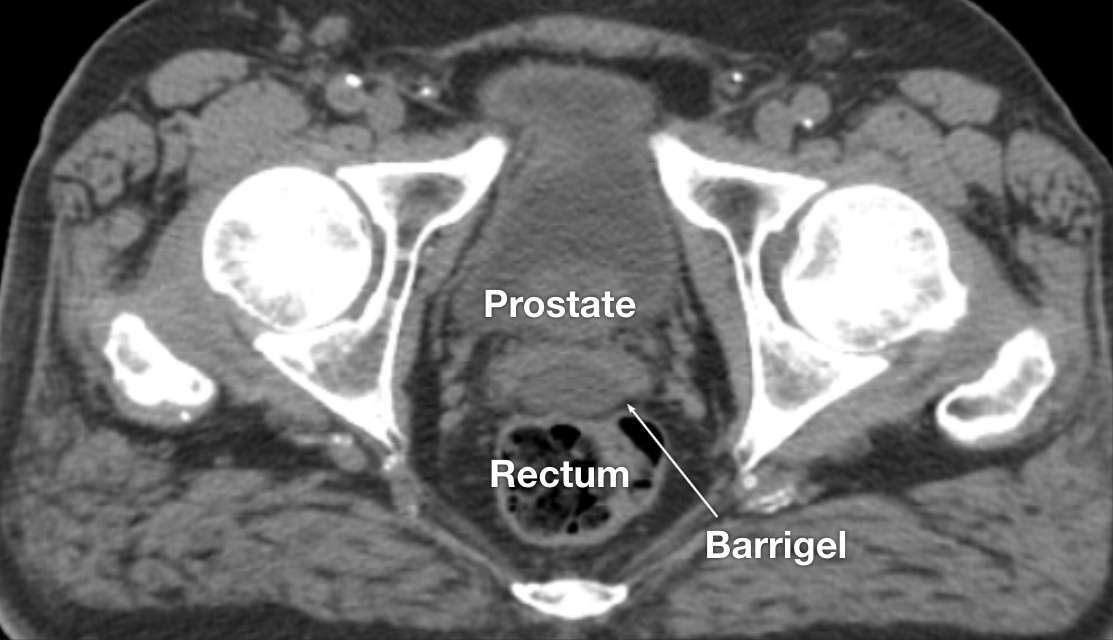

CT image courtesy of Escalarta López Ramírez, MD

Radiation Oncologist; Madrid, Spain